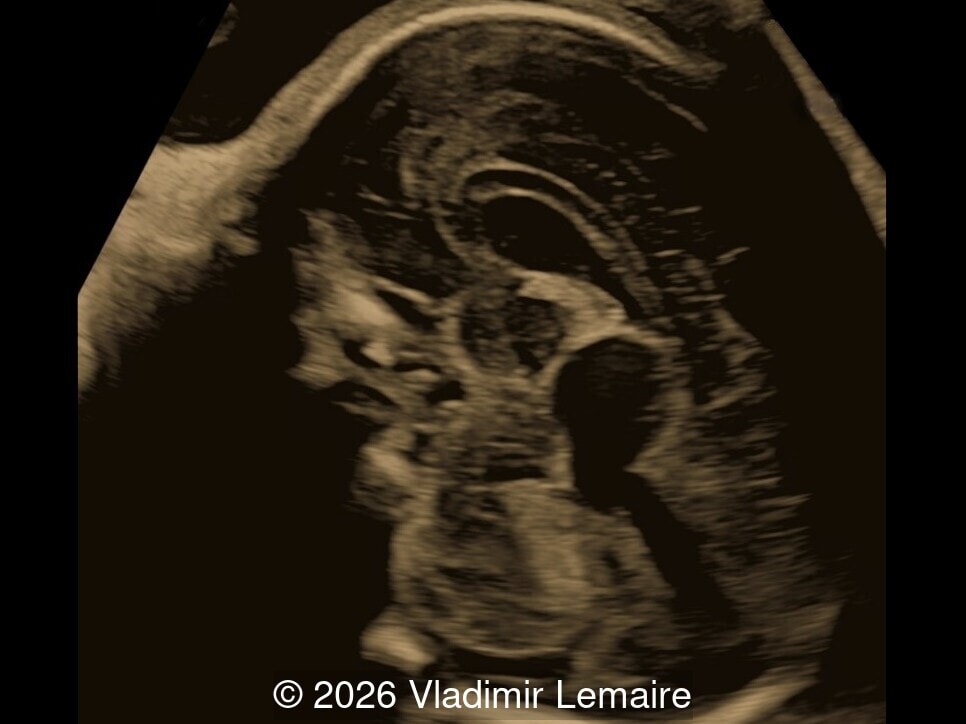

Axial 3D glass-body mode of the intracerebral vasculature.

Image 2 Axial 3D glass-body mode of the intracerebral vasculature.